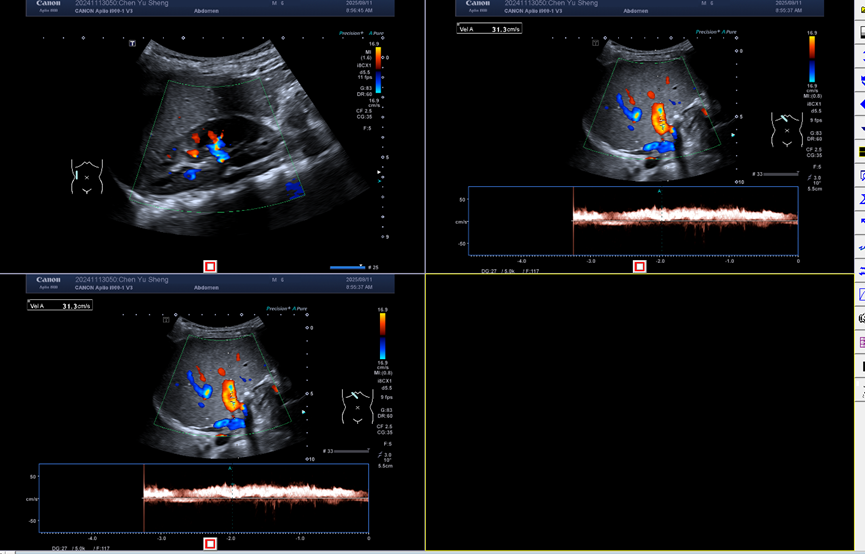

超声(2021.08.08)

肝脏实质性占位病变,考虑肿瘤合并破裂出血。门静脉声像异常,考虑门静脉血栓形成。